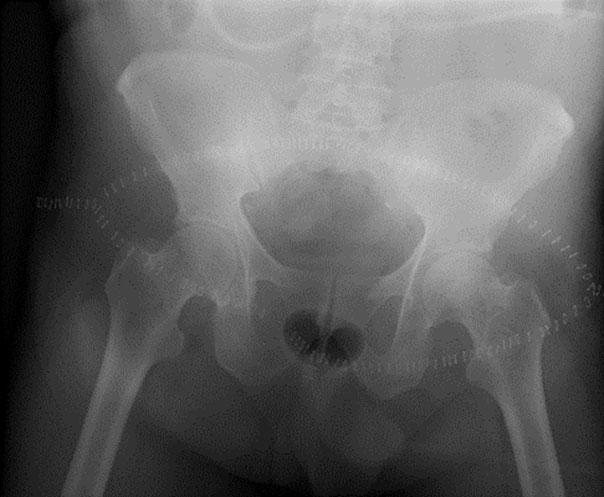

Ameliyat sonrası: Birinci sakrum distalinden itibaren rezeksiyon yapıldığı görülmekte